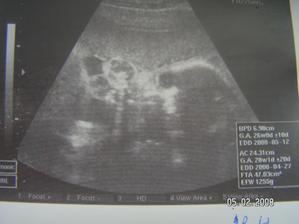

Tak jsme zpět z poradny.Jestli to bude kluk nebo holčička nevíme,protože miminko překřížilo nožky a nechtělo se ukázat.Za to na mamku krásně mávalo,tak to pan doktor zvěčnil-fotka je v albíčku.Měříme už 11cm!!!Zítra - 14.11. jdeme na tripple testy a taky na kontrolu,mamce totiž začalo nějak tvrdnout bříško,tak to pan doktor raději zkontroluje.Snad je všechno v pořádku.///Tak dneska 14.10.-na kontrole všechno v pořádku,jen placenta je trochu moc dole,ale to by se mělo do dvou měsíců upravit,mimi je o pět dní menší,ale krásné.(viz. foto).Dostali jsme magnézko na to tvrdnutí.Nabrali mi krev na tripple testy,tak se bojím,aby to bylo v pořádku.///Tak na testech jsme měli nakonec něco mírně zvýšené,ale celkem ještě v normě,tak doufám,že 12.12. na velkém genetickém UZ bude všechno v pořádku.A třeba se už konečně dozvíme,co to vlastně čekáme.///Tak jsme byli na genet.UZ-všechno je naprosto v pořádku!!!Mimi váží 360g a měří 25cm.Jsme 20+5tt.A víme,co to bude!Holčička!!!///Narazila jsem na úžasný kočárek,byla jsem z něho tak unešená,že jsme ho malé Fazolce museli pořídit.///7.1.-KO v poradně.Princezna má už 633g!!Všechno je v pořádku.Příští týden na cukrovkový test-FUJ!Můj váhový přírustek zatím 4,5kg-24+6tt.///Včera-4.2. kontrola v poradně.Všechno v pořádku.Vážíme 1255g a měříme přes 30cm.Můj váhový přírůstek - 29.tt.-asi 5,5 kg.///3.3.2008-velký UTZ,všechno v pořádku,akorát mám špatný krevní obraz,takže budeme zobat železo.Můj váhový přírůstek 7kg-33.tt.////